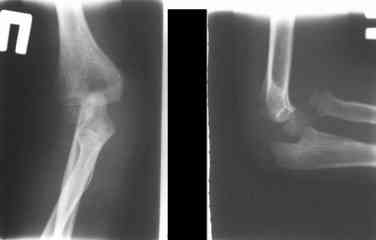

Иллюстрация к лечению застарелого повреждения Монтеджиа

Пациентка клиники детской травматологии ЦИТО

Многоуважаемые коллеги, всем большое спасибо!!! Да, здесь было повреждение Монтеджиа, когда нарисовал скиаграмму все стало понятно. Мне очень понравились рекомендации Константина Требухина, только немножко видоизменил; я считал так, если деформацию исправить то локт/кость должна удлиниться, и во вторых, если на аппарате низвести лучевую кость, то может наступить позиционное несоответствие в дистальном радиоульнарном сочленении. 28.02.08г операция - шарнирная остеотомия локтевой кости на уровне деформации, далее вскрыт плечелучевой сустав, удалены рубцовые тканы, после исправления варусной деформации и создания физиологического изгиба локтевой кости головка луча легко вправился, из части рубцовой ткани сделана пластика кольцевндной связки, трансартикулярная фиксация спицей, локтевая кость двумя спицами.

Уважаемый Абдурашид, у ребенка имеется последствие повреждения Монтеджиа. В данном случае в связи деформацией локтевой кости показано двух этпаное лечение. Первым этапом в аппарате Илизарова проводиться низведение головки лучевой кости. Вторым этапом проводится корригирующая остеотомия локтевой кости на границе средней и верхней трети с остеосинтезом либо в аппарате Илизарова, либо стержнем Богданова. Востанавливается нормальная .иогнутая форма локтевой кости. Далее проводится ревизия луче-плечевого сочленения. Иссекаются рубцовые ткани. Головка вправляется и фиксируется спицей на 3-4 недели (либо ллавсановой лентой).

Без коорегирующей остеотомии локтевой кости рецидив вывиха головки лучевой кости неизбежен.

На рентненграмме видна деформация локтевой кости на границе верхней и средней трети. Ведь там был перелом.